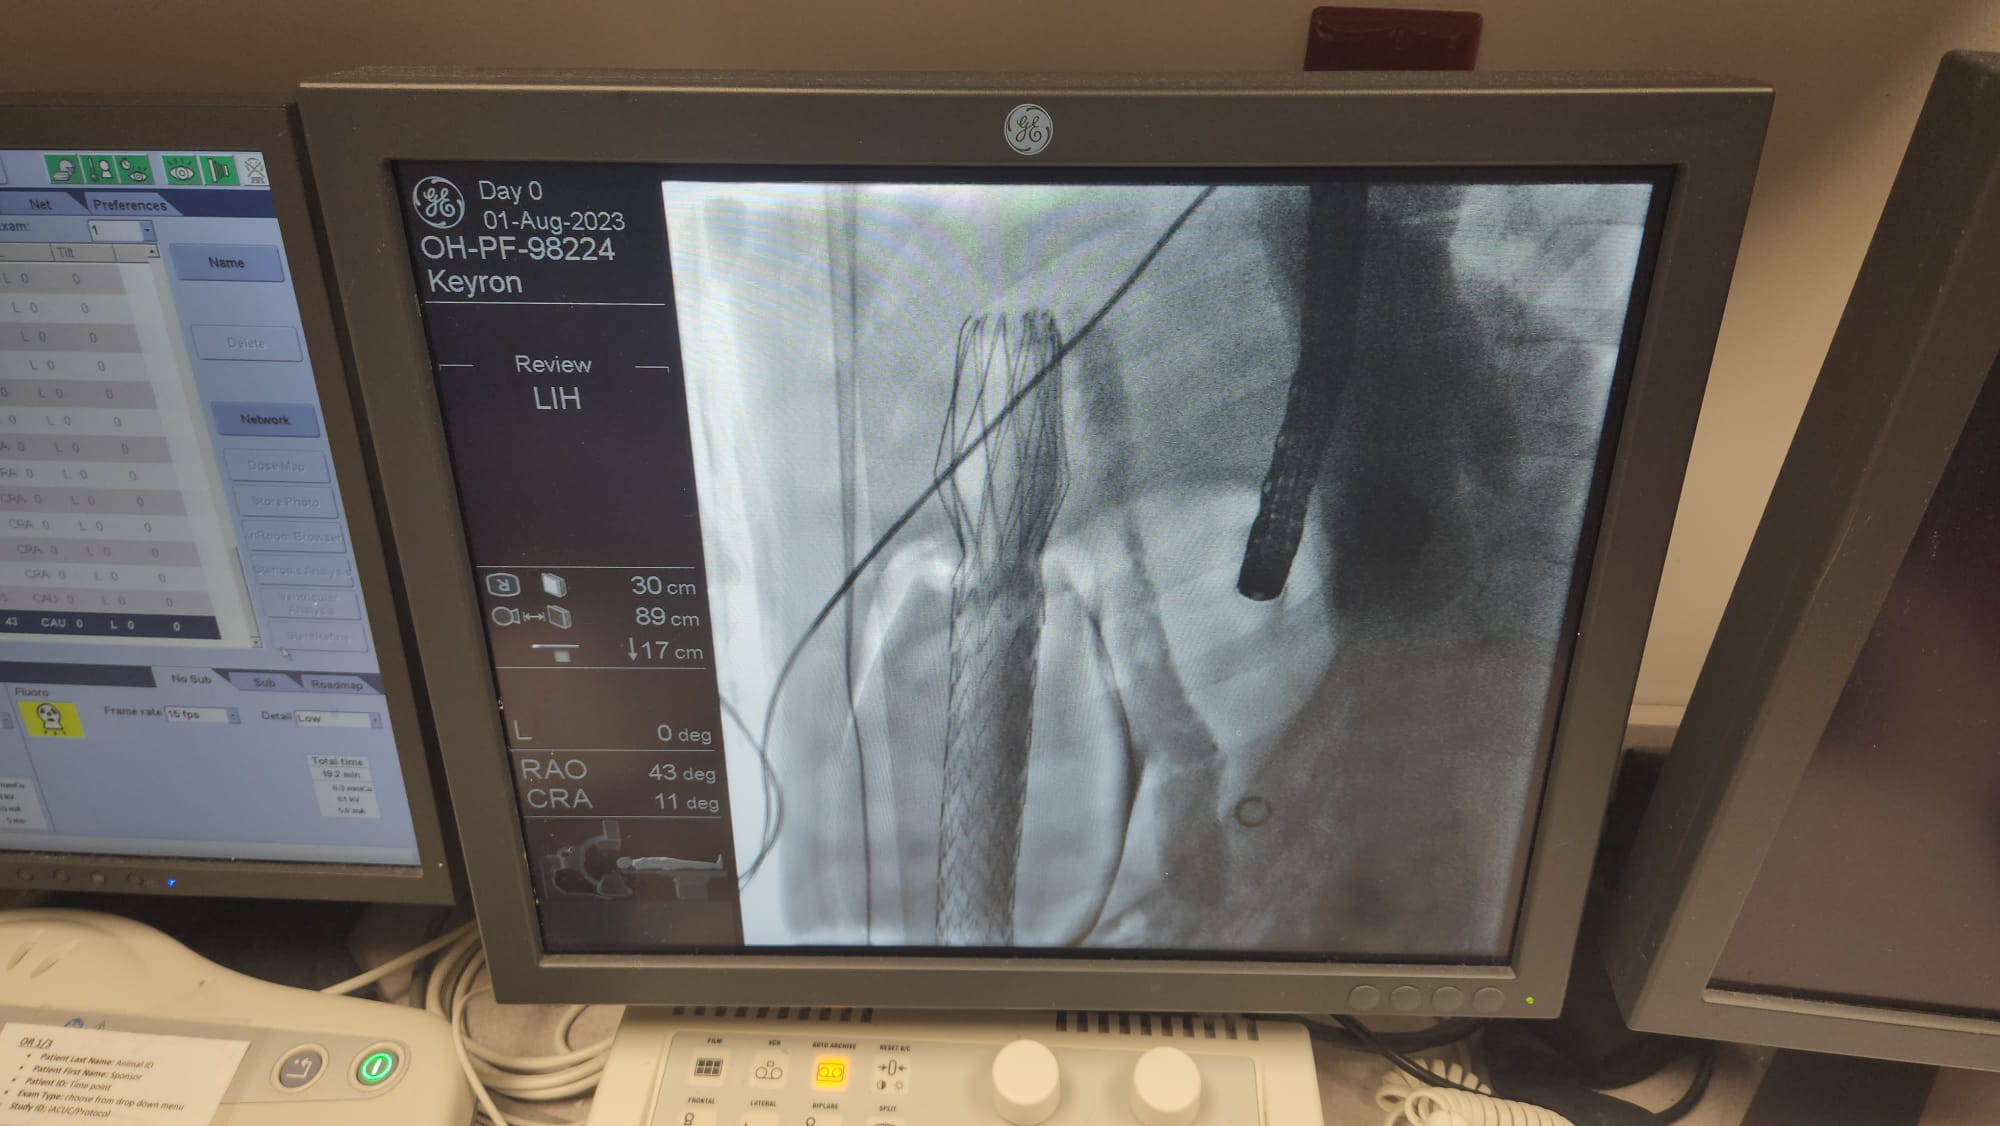

Long-Term Safety & Efficacy in Swine

Proven Long-Term Safety

Proven Correct and Stable Long-Term Positioning